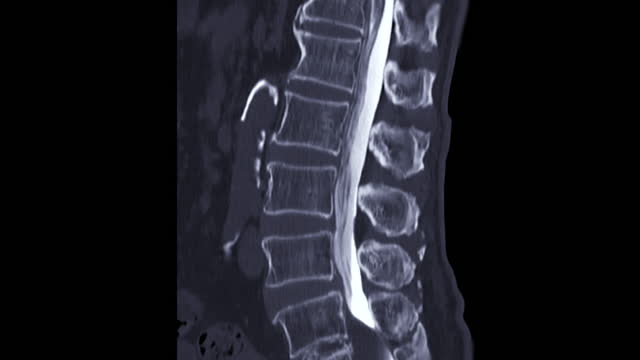

척추협착증은 척추의 추간공이 좁아져 척추 신경이 압박되는 질환입니다.

척추협착증의 증상이 심한 경우에는 수술 치료가 필요할 수 있습니다. 수술을 통해 추간공을 넓히고 압박을 완화시킴으로써 증상을 개선시킬 수 있습니다. 수술은 진통 및 통증 완화 효과가 높지만, 항상 최후의 수단으로 고려되어야 합니다.